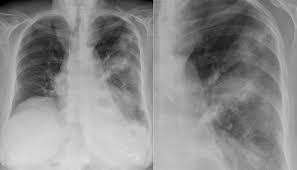

Mise à jour de la fiche 09/2011. Cette maladie infectieuse, potentiellement mortelle, touche généralement les adultes et les personnes en âge avancé. Vaccins, traitements et conseils pour lutter contre la légionellose) avec la fondation pasteur. Les grands signes séméiologiques de la radiographie thoracique. La radiographie pulmonaire confirme l'infection pulmonaire et la légionellose est prouvée par différentes méthodes possibles : Cette radiographie pulmonaire frontale montre une pneumonie bilatérale aiguë (maladie des légionnaires causée par legionella pneumophila). La radiographie de poumons et la recherche d'antigènes sont les deux examens permettant de poser le diagnostic. © gouvernement du québec, 2015.

Elles ont besoin d'une température comprise entre 20 et 50 degrés pour proliférer. Lalégionelloseest une infection respiratoire causée par des bactéries appelées légionelles. Cas confirmé de légionellose si : Elle fait parfois parler d'elle dans les installations collectives d'aération, de production d'eau chaude. Signalons que la maladie peut aussi être diagnostiquée en radiographie du thorax qui montre des condensations avec épanchement de la plèvre dans 1/4 des cas. La légionellose est une infection respiratoire causée par la bactérie legionella. Cette radiographie pulmonaire frontale montre une pneumonie bilatérale aiguë (maladie des légionnaires causée par legionella pneumophila). La radiographie pulmonaire confirme l'infection pulmonaire et la légionellose est prouvée par différentes méthodes possibles : Une radiographie de thorax permet de visualiser « par transparence » les poumons principalement, mais aussi la forme du cœur et les os du thorax (côtes et clavicules). Tous les cas de légionellose diagnostiqués doivent être déclarés à la fois par les médecins et les biologistes aux autorités. Les légionnelles se trouvent dans les eaux douces tièdes et chaudes des installations. Les légionelles se développent dans tous les milieux hydriques. 1979) dont la plus connue est legionella pneumophila.